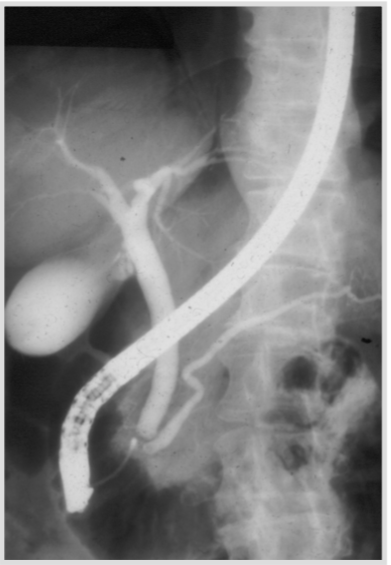

A 61 year old man complains of weight loss and is deeply jaundiced. He was found to have high liver enzymes and high GGT and ALP. An ERCP was performed which showed dilated bile duct without presence of stones. What is the likely diagnosis?

Pancreatic adenocarcinoma